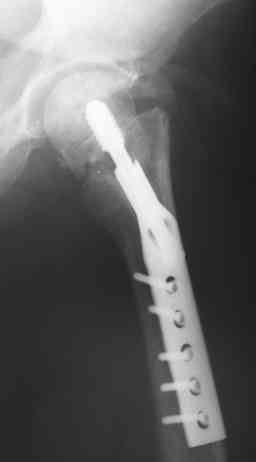

Вальгизирующая остеотомия по Marti с латерализацией, фиксация клинковой

пластиной (см. рис.) - хотя результат менее предсказуем, чем при эндпротезировании.

Поэтому отбрасывая все остальное, считаем, что Intertrochanteric valgus osteotomy или Межвертельная вальгусная остеотомия создает те необходимые биомеханические преимущества, которые восстановят измененную биомеханику.

Среди всех остальных этот вариант является менее инвазивным, отличный результат от 75-90%, отсутствует дополнительный риск повреждения кровоснабжения головки бедра, и главное - биомеханические преимущества.

Технически все делается внесуставно, без вскрытия места ложного сустава, в положение больного на спине, для облегчения работы ближе к краю операционного стола.

На вертеле делается "срез" в латеральном кортекса для клинка пластины и специальное долото вводится под 90-градусным углом к бедру по заранее приготовленному предоперационному плану.

Делается межвертельная остеотомия с удалением клина в 20-30 градусов в зависимости от шеечно-диафизарного угла, а все остальное сделает 120 градусная Blade Plate.

Для предупреждения вальгуса механической оси конечности необходима латеризация бедра, кусок кости от остеотомии, уложеный между пластиной и латеральным кортексом, латерализует бедренный диафиз.

На представленных снимках некоторые моменты, предоперационный план, латерализация, расчет длины, ориентир для введения и наборы.